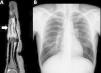

Varón de 42 años, natural de Marruecos, sin antecedentes de interés. Acudió a consultas de Atención Primaria por un cuadro de un año de duración de tumefacción en la falange media del cuarto dedo de la mano izquierda, no dolorosa en reposo pero sí a la presión. No refería antecedentes traumáticos ni ninguna otra sintomatología. Externamente, la piel y el aspecto de la región referida eran rigurosamente normales. Se decidió realizar una radiografía del dedo afecto, en la que se observaron múltiples lesiones óseas líticas con morfología en «panal» en la falange media (fig. 1). Ante estos hallazgos, el servicio de Radiodiagnóstico recomendó completar el estudio con una RM de mano, que confirmó estos hallazgos y valoró mejor la extensión de los mismos, así como el respeto de los espacios articulares (fig. 2A). Ambas pruebas, tanto la radiografía como la RM, plantearon el diagnóstico de sarcoidosis ósea. Se completó el estudio con una radiografía simple (fig. 2B) y una TC torácica, que demostraron adenopatías hiliares bilaterales y un área en vidrio deslustrado en el lóbulo medio. Se remitió al paciente al servicio de Neumología para la toma de biopsia. Tras la biopsia transbronquial de una de las adenopatías, el resultado anatomopatológico fue compatible con sarcoidosis. El diagnóstico final fue de sarcoidosis estadio ii con afectación ósea.

Radiografía simple posteroanterior (izquierda) y lateral (derecha) focalizada en el cuarto dedo de la mano izquierda. Se aprecia una desestructuración de la cortical de la falange del dedo medio a expensas de un patrón lítico de aspecto microcístico, similar a un patrón en panal con respeto de los espacios articulares.